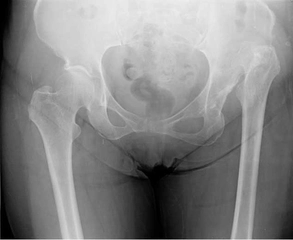

Düşme Sonucu Kalça Kırığı Riski Nasıl Azaltılır?Düşme, özellikle yaşlı bireylerde kalça kırıkları gibi ciddi yaralanmalara yol açabilen önemli bir sağlık sorunudur. Bu makalede, düşme sonucu kalça kırığı riskini azaltma yöntemleri üzerinde durulacaktır. Düşme Nedenleri ve Risk FaktörleriDüşme olayları, çeşitli faktörlerin birleşimi sonucunda gerçekleşir. Bu faktörler arasında;